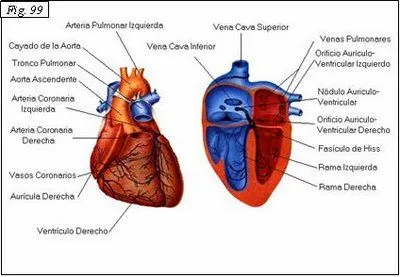

Dibujo del corazon humano con sus partes - Imagui